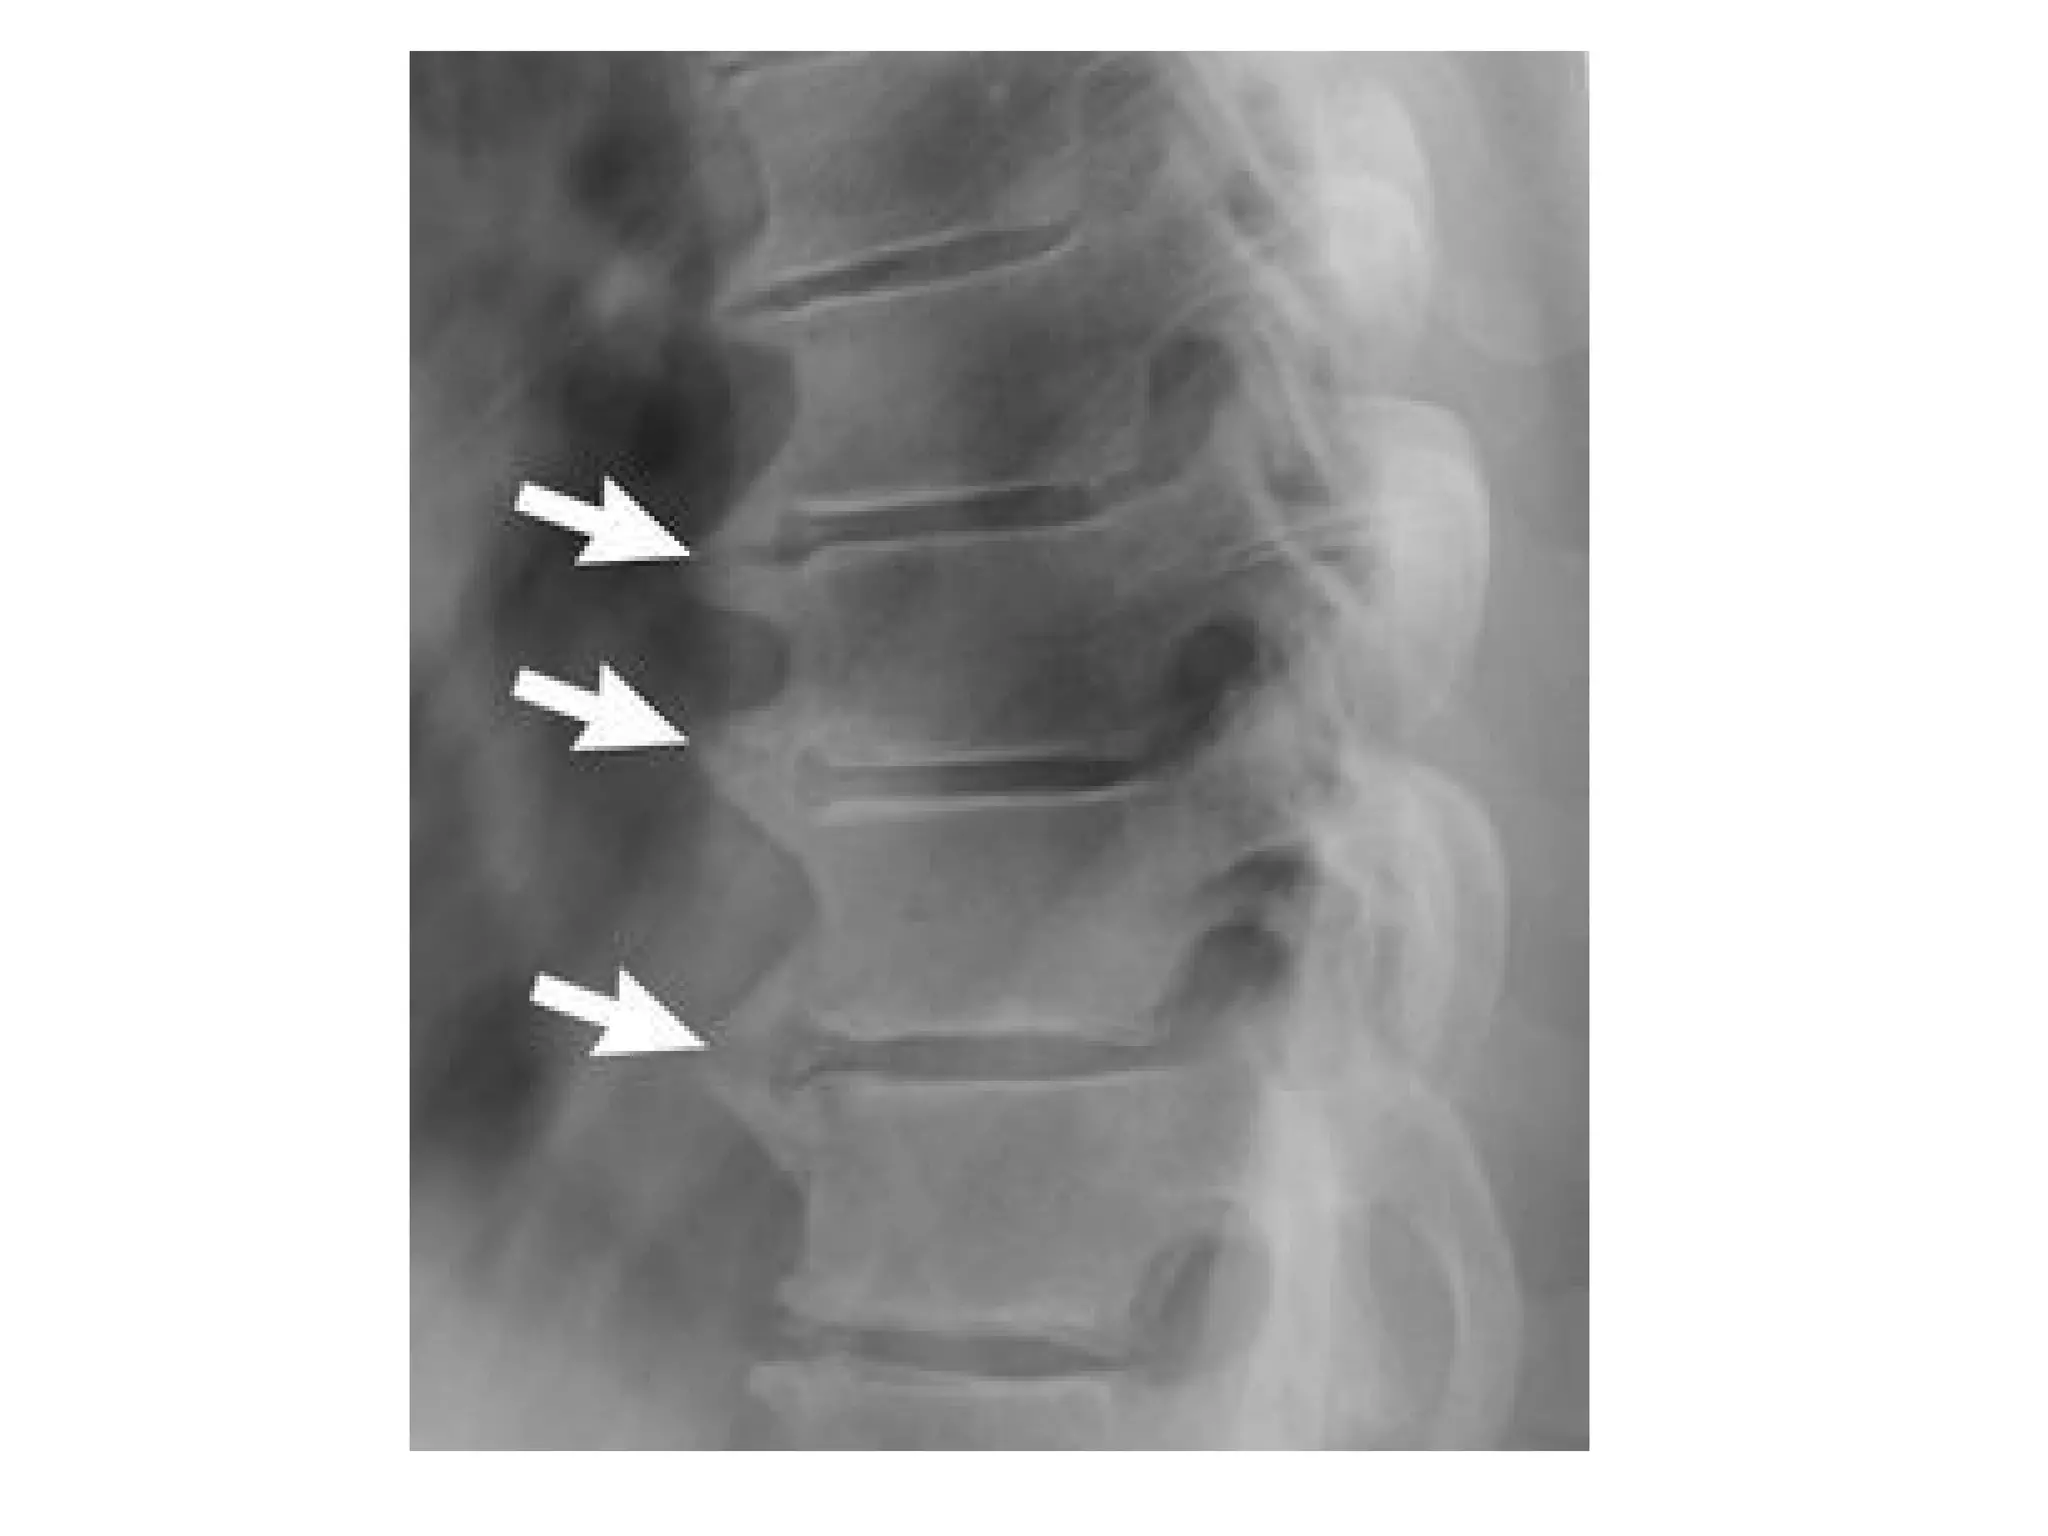

Severely decreased height of several disc spaces (white arrow) and anterior osteophytes

(bone spur , open arrow) ,sclerosis (3 arrowheads) of posterior facet joints

Spondylosis deformans , lateral radiograph of the lumbar spine reveals osteophyte

formation (arrows) , these initially extend in a horizontal direction and then in a

vertical one , severe apophyseal joint osteoarthritis is also present